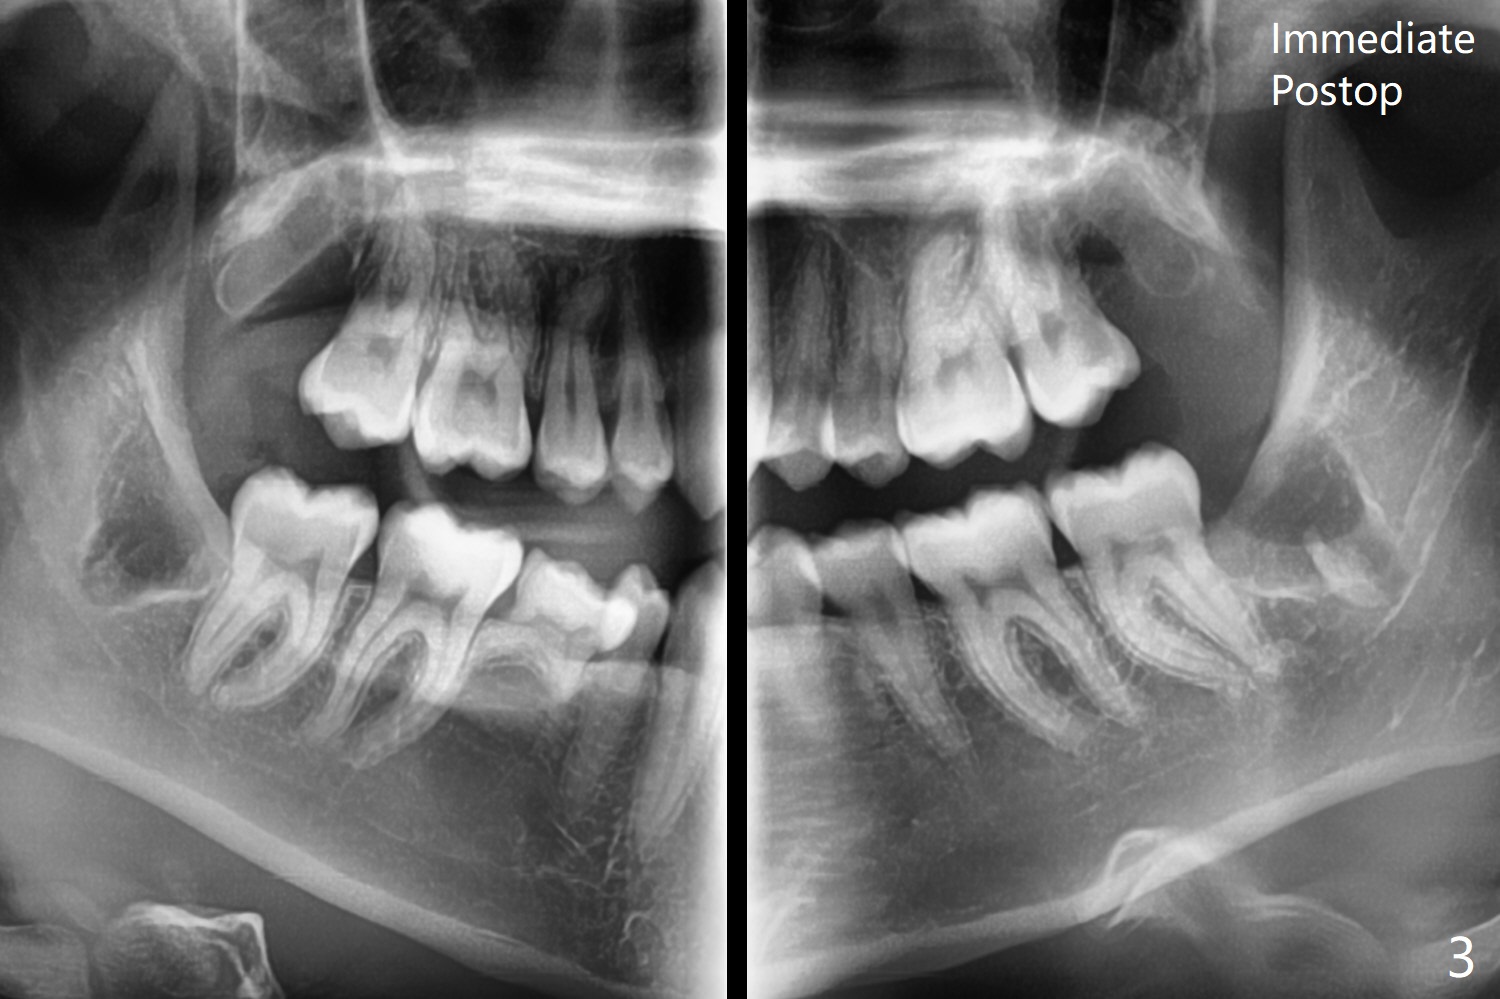

A 21-year-old nervous woman wants to have 4 of the 3rd molars extracted (Fig.1). To prevent dry socket, place collagen plug at #17 and 32. Take panoramic 4 Bitewings postop and preferably preop, since Fig.1 was taken on January 1, 2018 and #17 and 32 are close to the Inferior Alveolar Canals. In fact Osteogen plug is placed at #16 and 17 due to apparently severe bony defect affecting the neighboring teeth, while Collagen plug at #32.